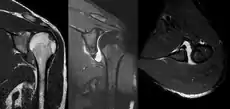

MRI of the shoulder after an anterior dislocation showing a Hill-Sachs lesion and labral Bankart lesion